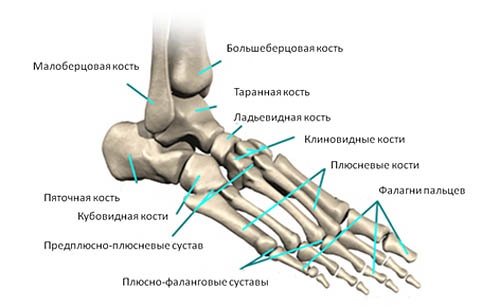

Анатомия стопы человека

- Плюсневые кости. Это пять длинных костей, которые находятся между костями предплюсны и фалангами пальцев. Основная функция плюсневых костей заключается в том, что они обеспечивают активное движение стопы, выполняя роль рычага при ходьбе, беге и прыжках;

- Фаланги пальцев ног. У первого пальца ноги имеется две фаланги, в то время как остальные пальцы состоят из трех. В общей сложности на каждой ноге насчитывается 14 фаланг;

- Три клиновидные кости. Они получили свое название благодаря клиновидной форме. Эти кости располагаются между ладьевидной костью и первыми тремя плюсневыми костями;

- Кубовидная кость (находится на внешней стороне стопы);

- Ладьевидная кость (имеет слегка уплощенную форму спереди и сзади, расположена в передней части стопы);

- Таранная кость (вторая по размеру среди костей предплюсны);

- Пяточная кость (сесамовидная кость стопы).